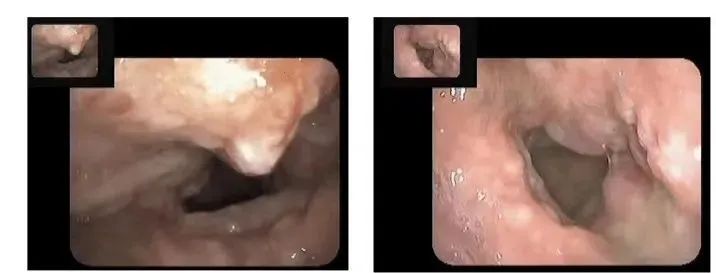

原本光滑的喉部,被肿瘤细胞占据

喉镜下,肿瘤得到有效控制,喉部肿瘤逐渐消失